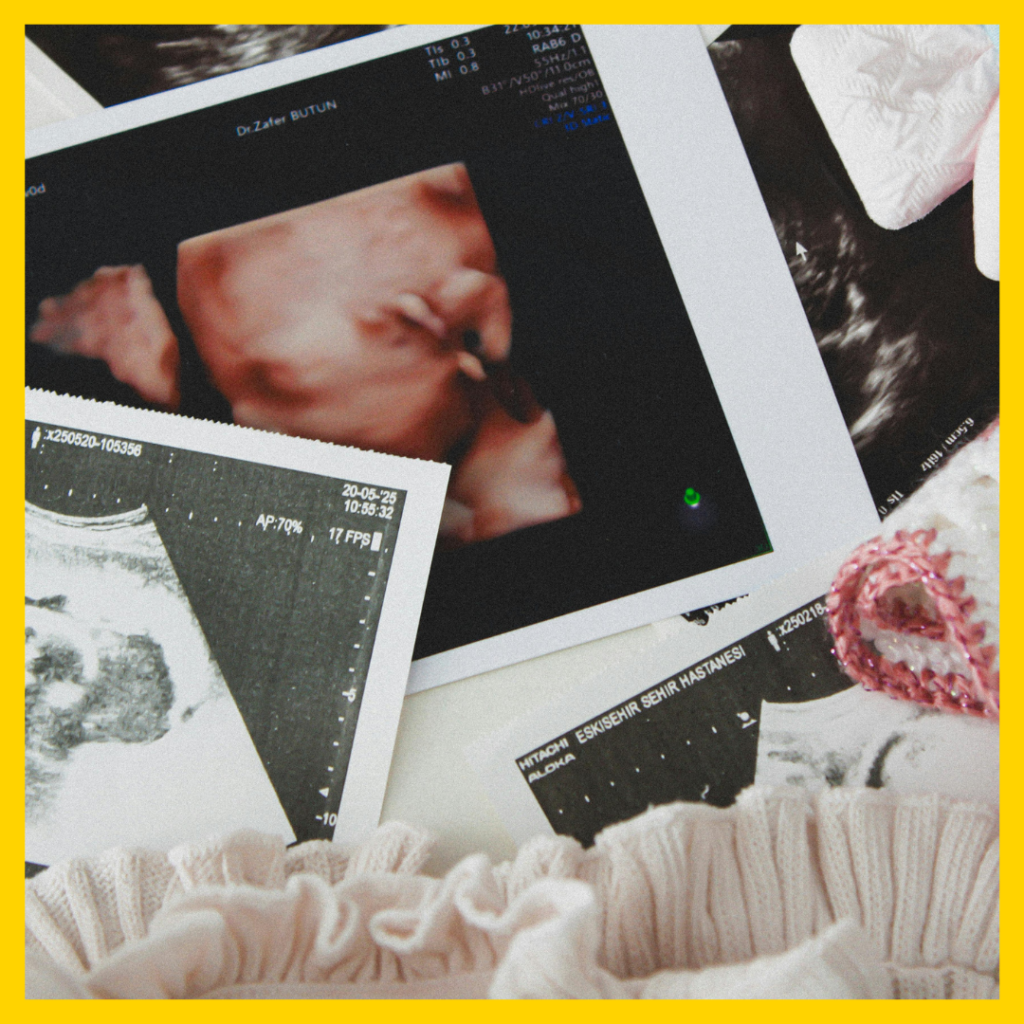

Ultrasound technology during pregnancy has evolved significantly, ranging from standard 2D imaging—which produces flat, black-and-white cross-sectional views—all the way to advanced 6D technology that leverages high-definition rendering and AI-enhanced image processing. In simple terms, 3D adds depth to create still surface images, 4D introduces live-streaming video to capture fetal movement in real time, while 5D and 6D refine lighting, skin tones, and clarity to produce remarkably realistic and lifelike images of the unborn baby. It is important to understand that 2D remains the primary diagnostic tool used by medical professionals, whereas the higher dimensions (3D through 6D) are largely intended for parental bonding and keepsake purposes.

What it is: Instead of a single flat plane, the machine captures sound waves from multiple angles (three planes: height, width, and depth). A computer then stitches these together to create a still, three-dimensional photograph.

What you see: A still, golden or sepia-toned image of your baby’s skin surface. You can see the curve of the nose, lips, and eyelids.

Primary use: Bonding and elective keepsakes. It helps parents visualize the baby’s face, but it does not show movement.

4D Ultrasound (The Live Movie)

What it is: This is essentially 3D in real-time. The machine takes multiple 3D images per second and plays them back as a video.

What you see: A moving video of your baby yawning, sucking their thumb, kicking, or turning their head.

Primary use: Emotional bonding and family viewing. This is the “live action” version of the 3D still.

pregnancy scan images